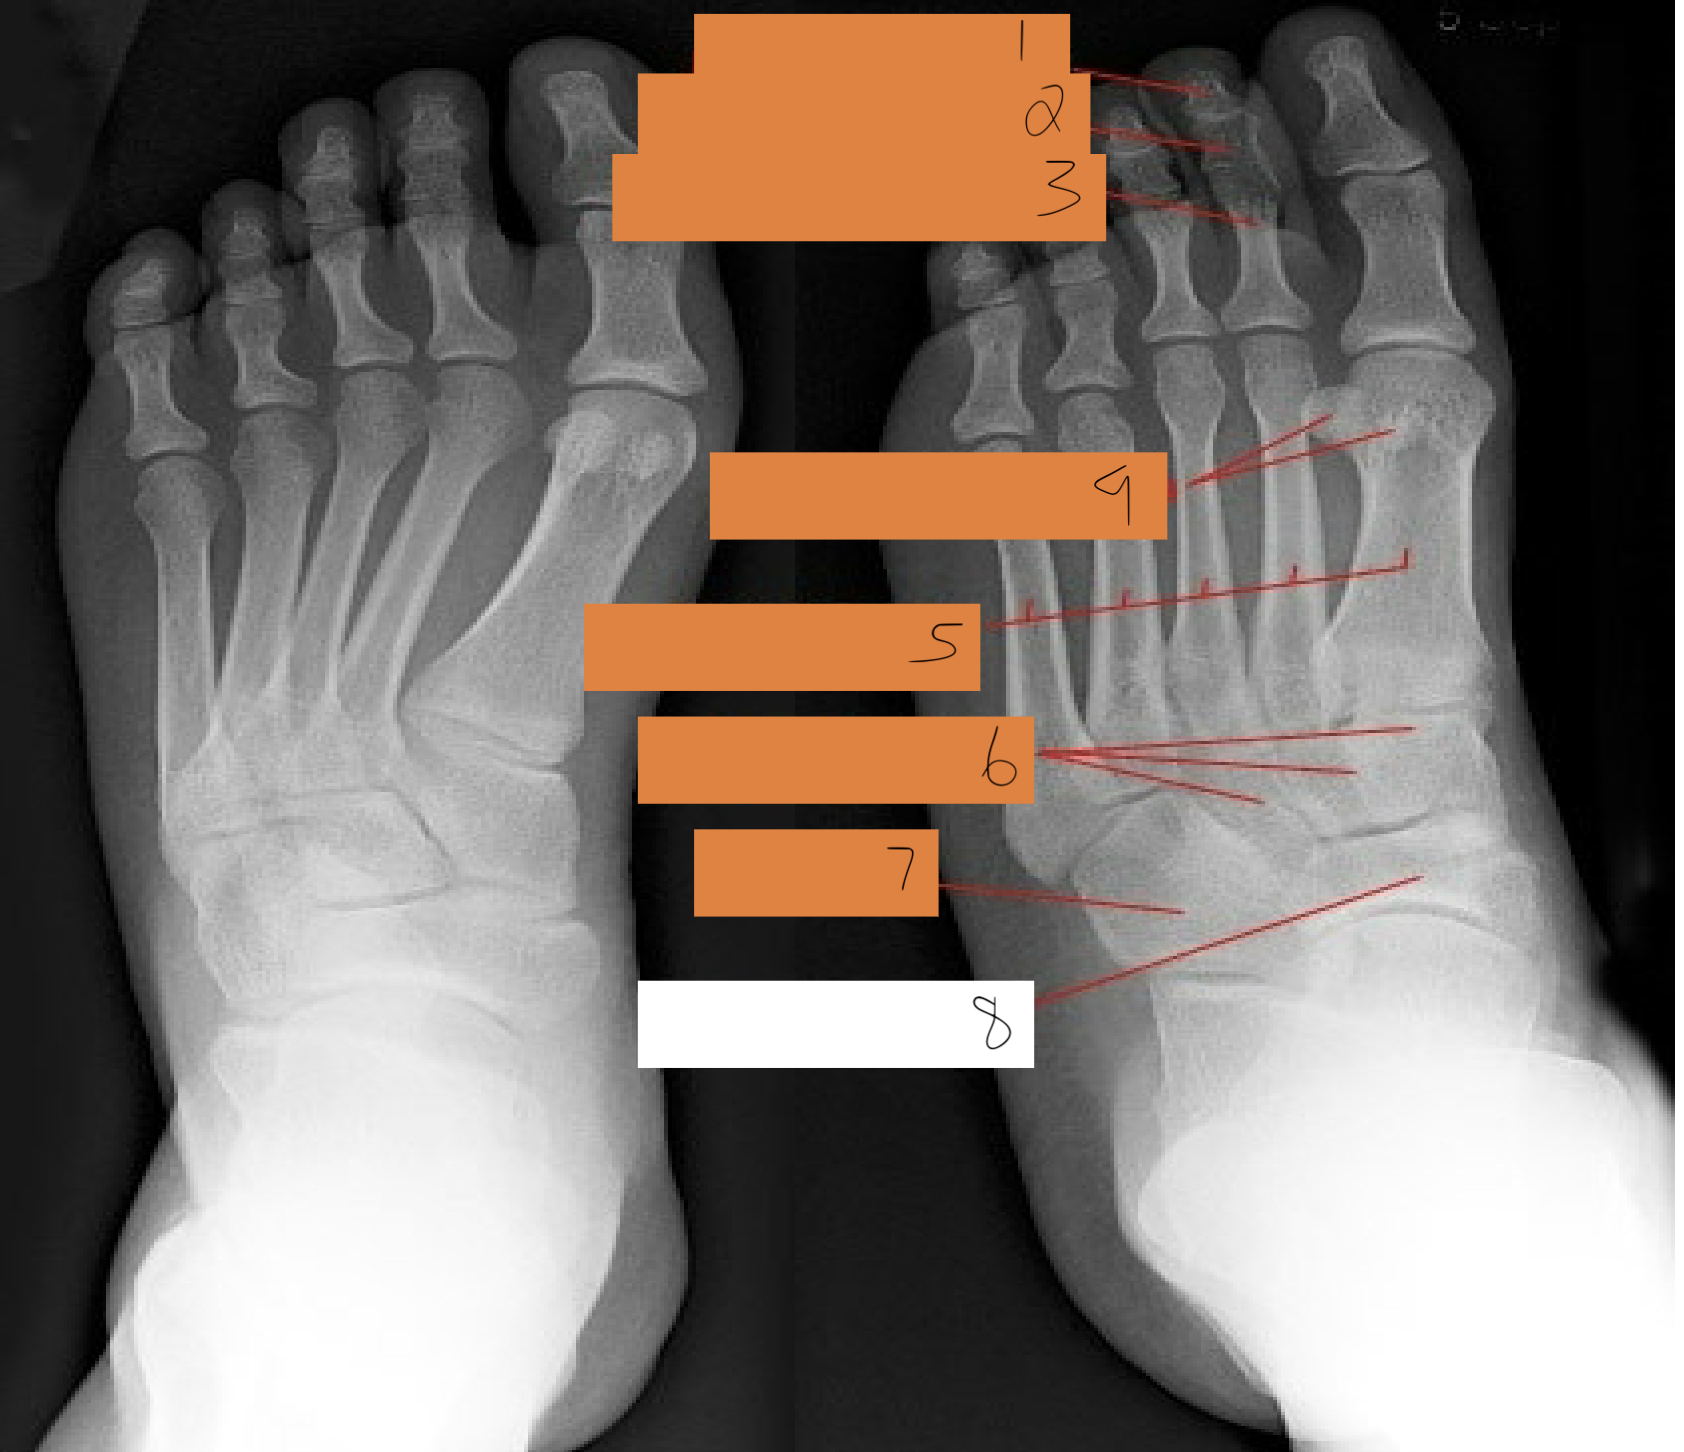

1

interphalangeal joint

2

proximal phalanges 1-5

3

metatarsophalangeal joints

4

sesamoid bones

5

first metatarsals

6

medial cuneiform

7

intermediate cuneiform

8

lateral cuneiform

9

navicular